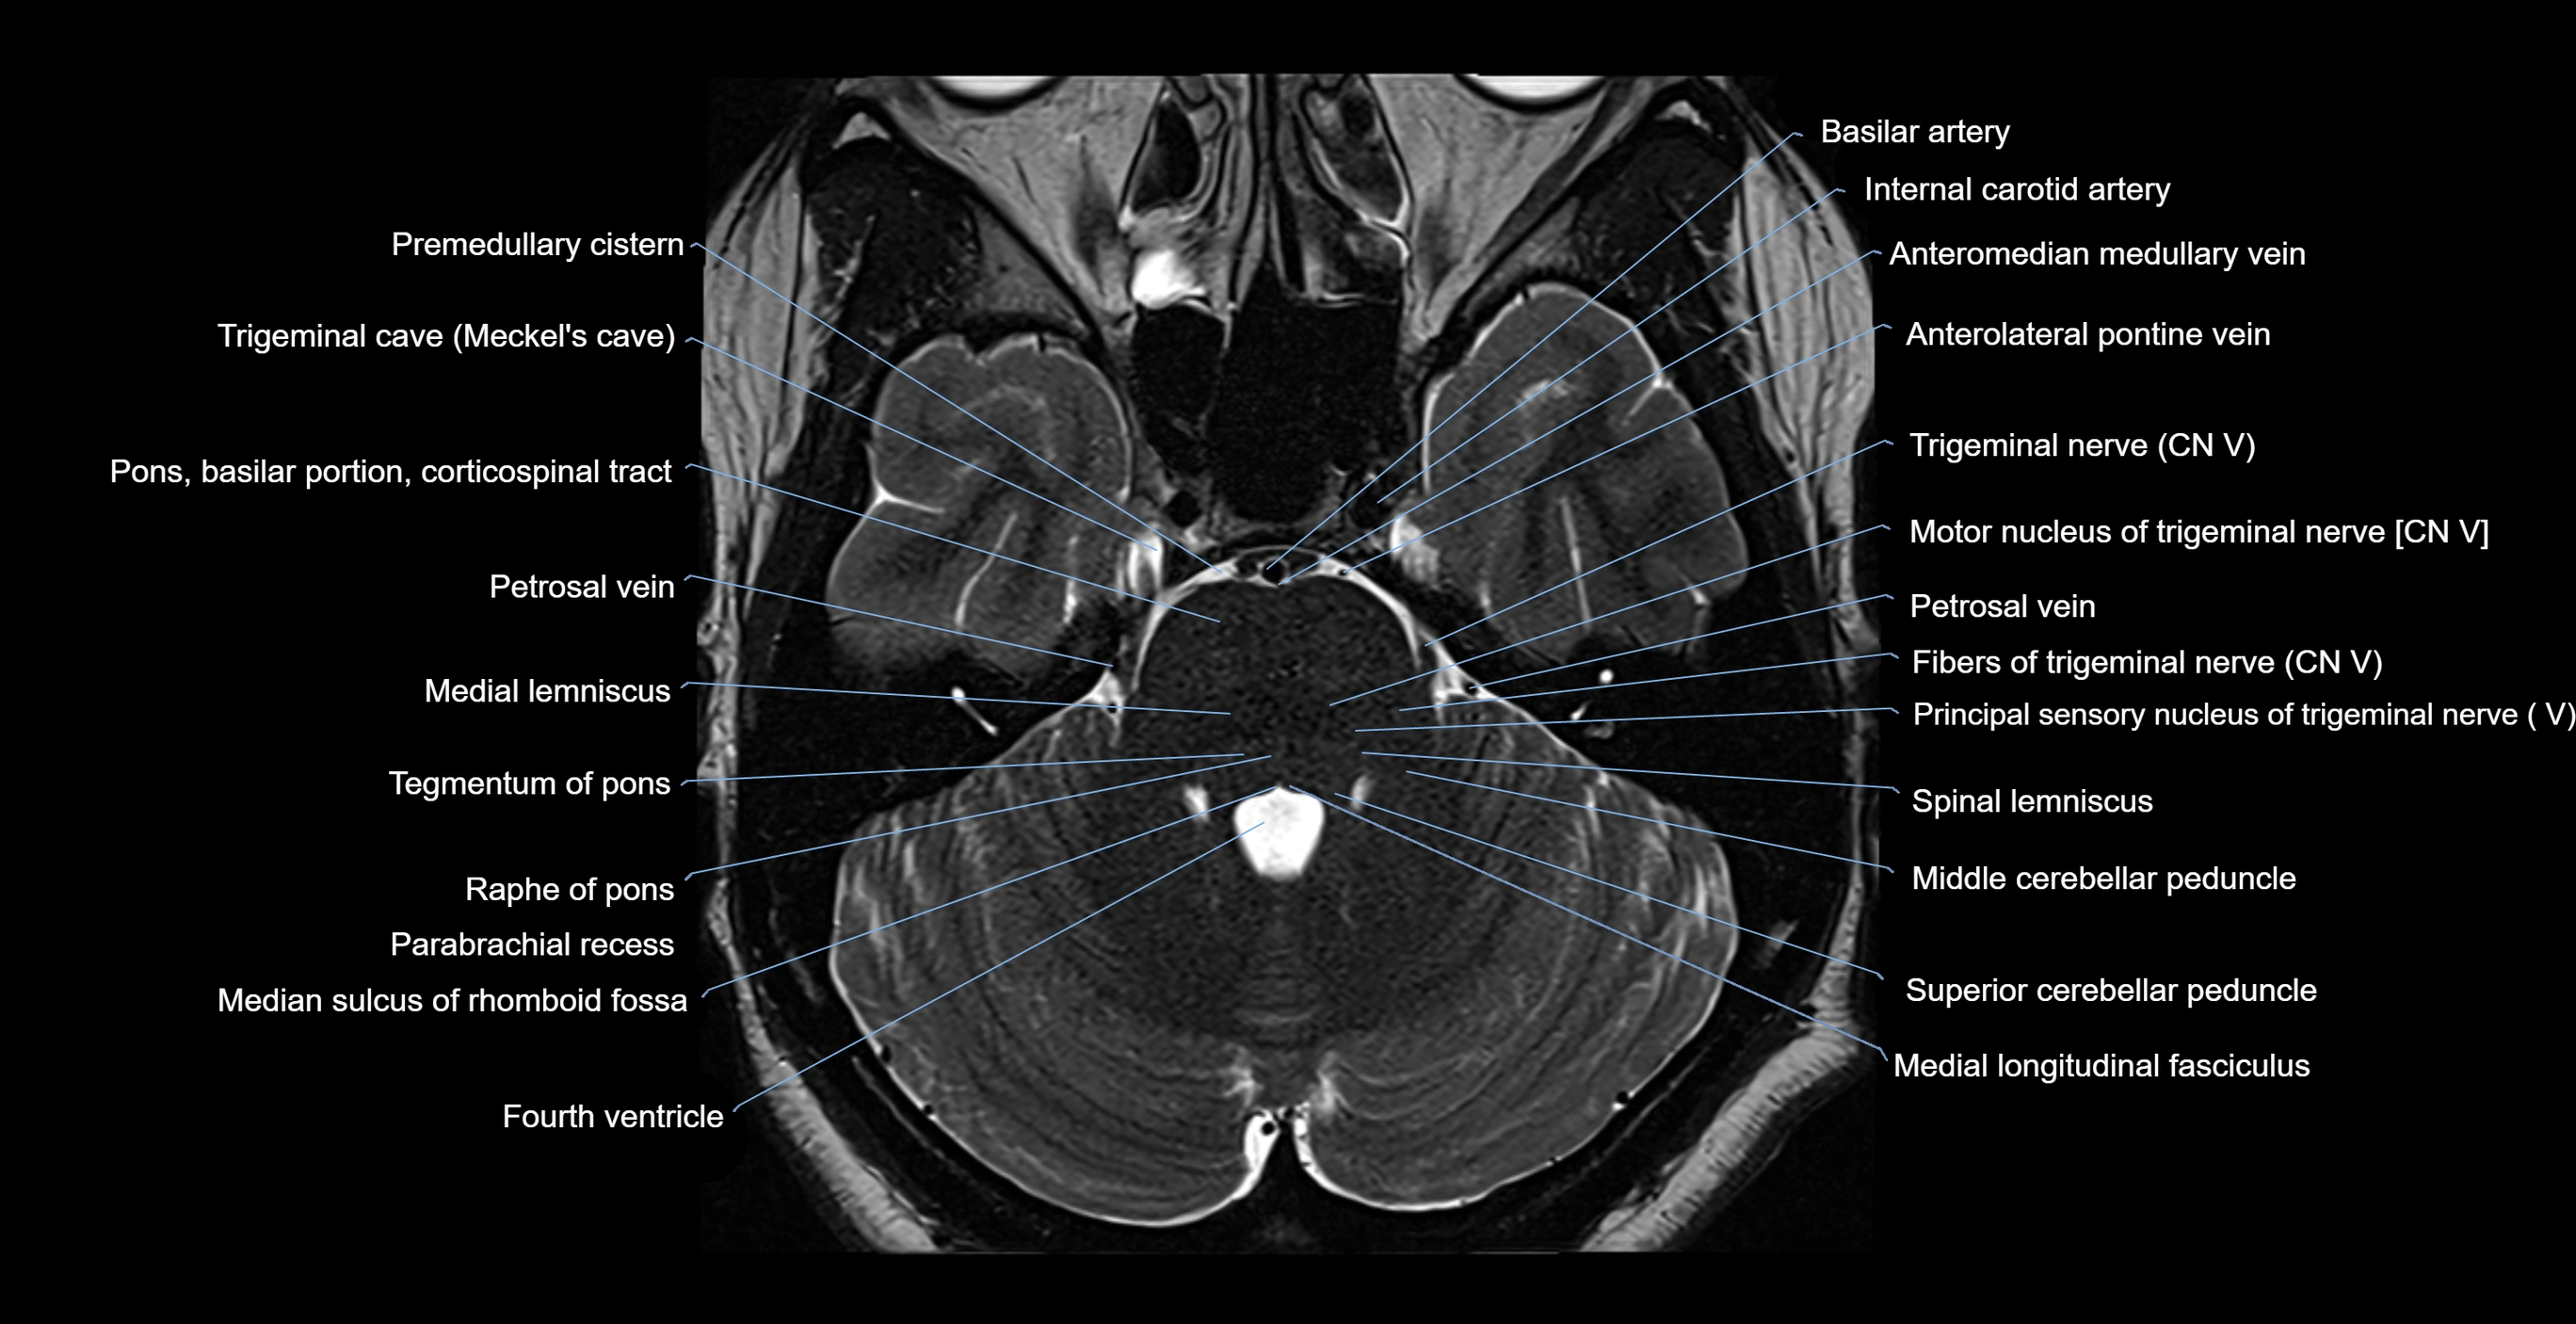

- Anterolateral pontine vein

- Anteromedian medullary vein

- Fibers of trigeminal nerve

- Medial lemniscus

- Medial longitudinal fasciculus

- Median sulcus of rhomboid fossa

- Middle cerebellar peduncle

- Motor nucleus of trigeminal nerve

- Parabrachial recess

- Petrosal vein

- Pons (basilar portion)

- Pontine nucleus

- Principal sensory nucleus of the trigeminal nerve

- Principal sensory nucleus of trigeminal nerve

- Raphe of pons

- Spinal lemniscus

- Superior cerebellar peduncle

- Tegmentum of pons

- Trigeminal nerve (Cranial nerve V)